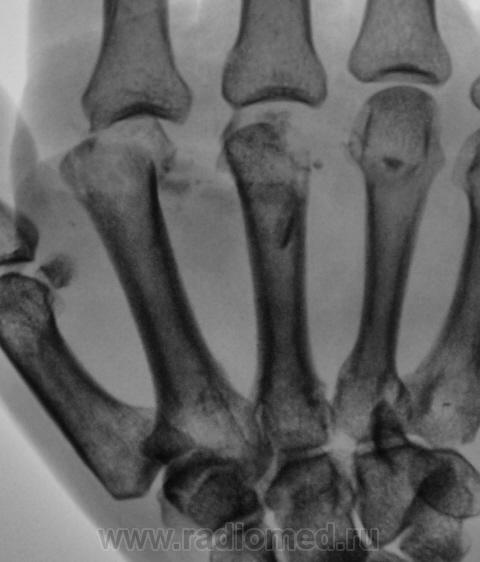

перелом 2,3,4 пястных костей.

Люк - это ближе к истине, а вот при "крепкой челюсти", как правило, ломается 5-я...

И 5-я пястная цела была

Значит кулак сжат нормально и удар поставлен правильно, а вот у любителей всегда ломается 5-я...

Истины не знаю, но утверждает, что падал на кулак.